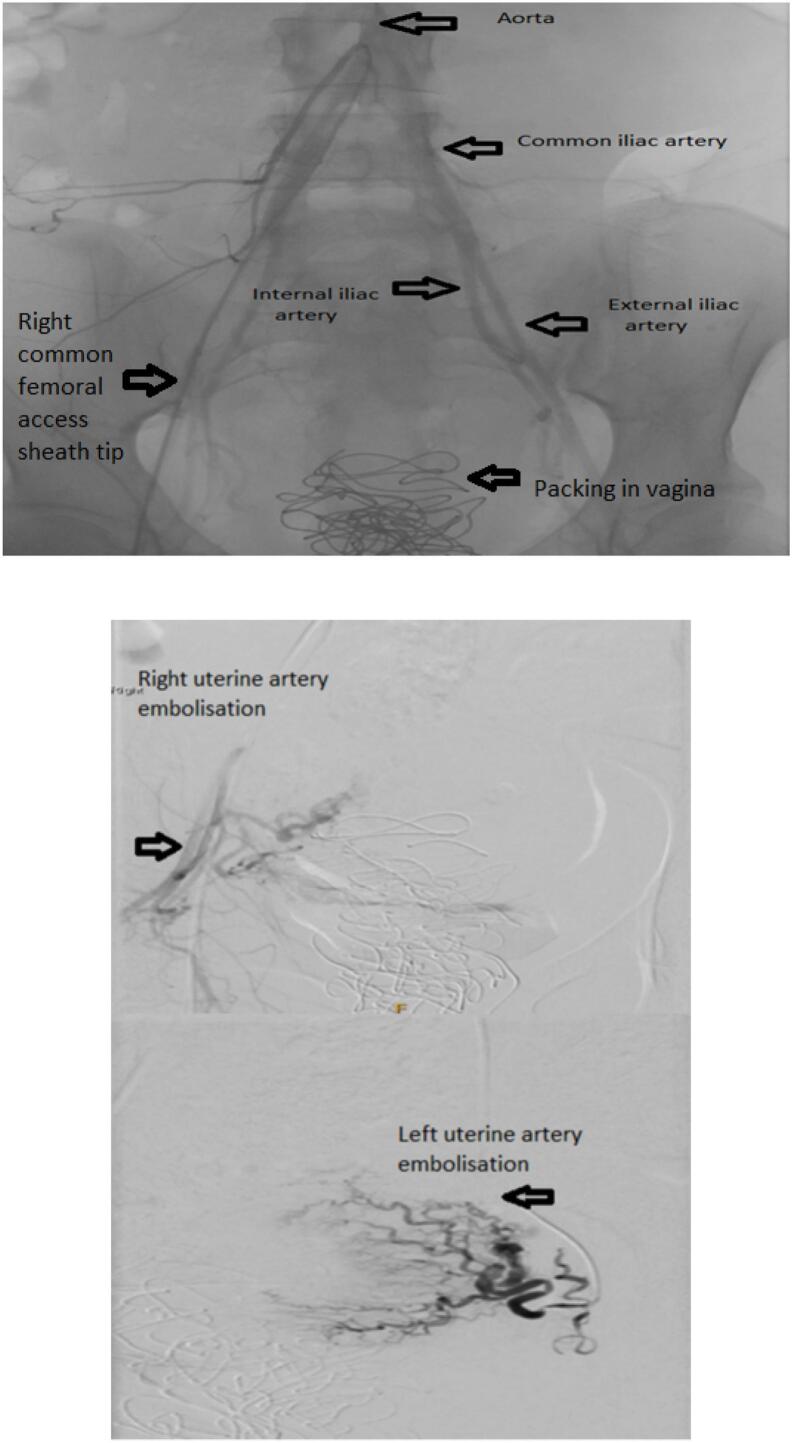

Subinvolution of the placental site can lead to severe post-partum haemorrhage, though it is a rare cause of the condition. Subinvolution of the placental site is an abnormal persistence of widely dilated uteroplacental spiral arteries in the absence of retained products of conception, and is associated with an increased risk of maternal morbidity and mortality. This report presents a case of an uneventful caesarean section that was followed by multiple presentations of major secondary post-partum haemorrhage, with a subsequent diagnosis of subinvolution of the placental site on histopathology. The patient was eventually treated with uterine artery embolisation after trials of medical and other interventional measures.